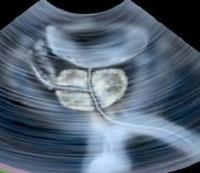

سونوگرافی داپلر یک روش تصویربرداری است که برای نشان دادن حرکت خون در رگ‌های خونی مورد استفاده قرار می‌گیرد و برای این کار از امواج صوتی استفاده می‌شود.

سونوگرافی داپلر(dopplerیک روش تصویربرداری است که برای نشان دادن حرکت خون در رگ‌های خونی مورد استفاده قرار می‌گیرد و برای این کار از امواج صوتی استفاده می‌شود. سونوگرافی داپلر به پزشکان کمک می‌کند تا بدون استفاده از اشعه‌ی ایکس یا هرگونه تزریق، بتوانند از آنچه درون رگ‌های بیمار در حال روی دادن است اطلاعات لازم را بدست بیاورند.